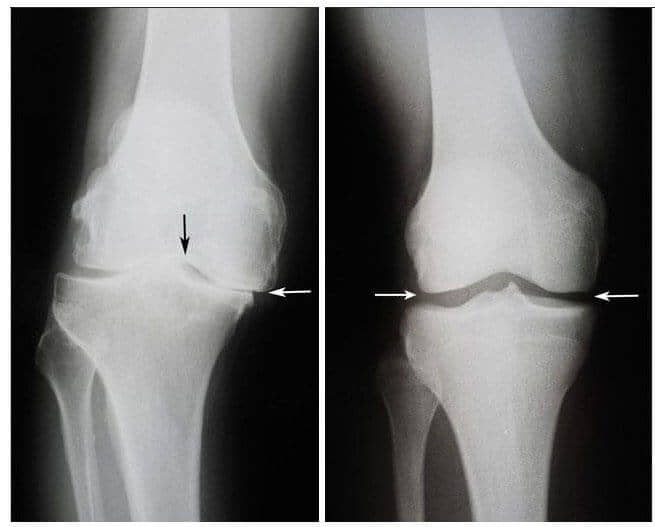

Onda se dogodilo čudo. Ovaj doktor je počeo svaki dan dolaziti kod Nermine i mazao je ovom ljekovitom mašću. Nekoliko sedmica kasnije, uspjela je da ustane iz kolica i da sama ode kod doktora. Nakon šest sedmica, zglobovi Nermine Arnautović su se potpuno oporavili od osteoartritisa. Snimci su to pokazali.

S lijeve strane: Snimak zgloba koljena Nermine

Arnautović, 75. Hrskavično tkivo je potpuno uništeno. Preporuka

doktora je da se uradi operacija koljena i da se zglob zamjeni

vještačkim.

S desne strane: Snimak zgloba

desnog koljena Nermine Arnautović nakon liječenja gelom Nautubone.

- Snimak ispod pokazuje tipičnu sliku oporavka zgloba koljena.